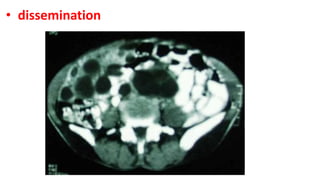

• dissemination

• Case presentation

• A forty five year old lady presented with chronic dull aching pain with

gradually increasing lump in the epigastric and pelvic region since 3 years.

A well defined, firm mass of about 20 Ɨ 20 centimeters was palpable in

epigastrium extending more on right hypochondrium, probably arising

from left lobe of liver. A similar mass was palpable in the hypogastrium

while multiple small nodular masses palpable in the right iliac fossa and

lumbar region. Detailed inquest revealed a 5 year old incidence of blunt

abdominal trauma, while working in her farm. The ultrasonography and

CT scan (See Figure 1) showed multiple thin walled cysts of varying size

involving left lobe of liver, peritoneal cavity, omentum and mesentery.

Cysts showing internal septae and peripheral tiny calcific foci were also

seen extending into pelvis around uterus, adnexae and retro-uterine

cervical region, markedly compressing distal descending colon, sigmoid

colon and rectum. Ileal loops were compressed and displaced superiorly.

Serology for hydatid cyst disease was positive with ELISA test.